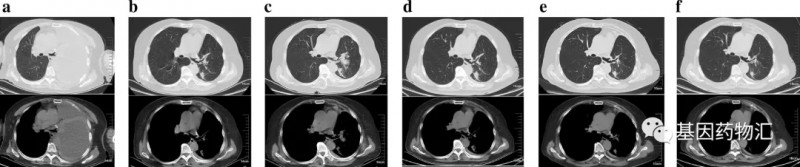

按照经验来说,Ⅲ期肺癌的治愈率也能有20%~30%,当然前提是患者按照规范进行术后的辅助治疗,并且按时复查、及时判断复发的情况。但这位患者拒绝了所有的辅助治疗,并且拒不复查,导致错失了治疗良机,直到3年多以后的2019年6月,她再因呼吸困难就诊的时候,再次被诊断为Ⅳ期的肺腺癌(下图a,可见大量胸腔积液;图b为胸腔穿刺后影像,可见左下叶2病灶)。

但最终,治疗效果不是很理想。接受治疗2个月后复查胸部CT时,患者的病灶仍在变大(图c),提示疾病持续进展。医生考虑为患者更换方案。

机缘巧合,使用拉罗替尼的机会来了。这一次,患者用上了针对她NCOR2-NTRK1融合突变的靶向治疗药物,TRK抑制剂拉罗替尼。用药仅1个月,复查时CT扫描(图d)就显示病灶体积缩小了30%,达到了部分缓解!

疗效良好,患者继续治疗。又2个月之后的检查结果显示(图e),患者的病灶体积缩小50%,且还在持续缩小,没有新发的转移病灶。至用药半年(图f),一部分病灶彻底消失。截至2020年12月,患者已经持续治疗超过15个月!

图a为患者2019年6月诊断时的CT影像,可见大量胸腔积液;图b为患者胸腔穿刺后的影响,排除胸腔积液干扰后,发现左下叶有2个转移性结节;图c为患者接受PD-1抑制剂卡瑞利珠单抗治疗2个周期后的影像,病灶仍在增大;图d为患者应用拉罗替尼治疗1个月后的影像,部分病灶开始缩小;图e为患者接受拉罗替尼治疗3个月后的影像,部分病灶不断缩小;图f为患者接受拉罗替尼治疗6个月后的影像,部分病灶缩小,甚至消失。